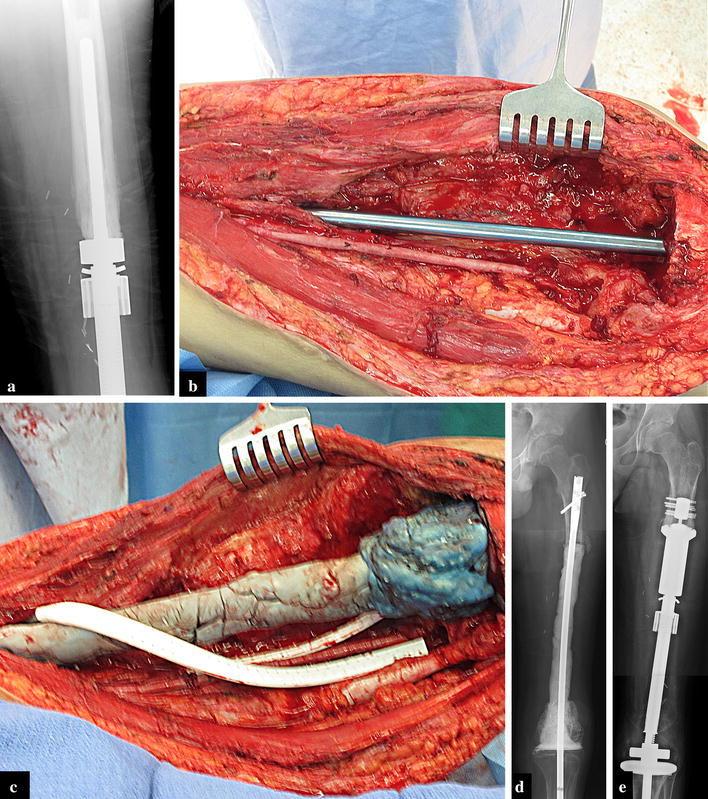

Limb-salvage for primary malignant bone tumors in pediatric patients presents a unique challenge when resection includes an active physis. Early expandable prostheses required open surgical procedures to achieve lengthening. Newer prostheses are capable of achieving expansion without open procedures through the use of an electromagnetic field. This study reports our results with 90 consecutive expansion procedures using the Repiphysis(®) prosthesis. We retrospectively reviewed the records of 20 patients (22 limbs) who underwent limb-salvage using the Repiphysis(®) prosthesis from 2003 to 2015. There were 9 males and 11 females with a mean age of 9 years and 9 months (6-16 years). Reconstruction included the distal femur in 11 cases, total femur in four, proximal tibia in three, proximal humerus in three, and total humerus in one. Complications were reviewed and functional scores were recorded using the MSTS/ISOLS system. Five patients had a second prosthesis implanted during the course of the study for a total of 27 prostheses. The mean follow-up was 57 (6-148) months. Four patients have not been expanded: three due to death prior to lengthening, and one patient who has not yet developed a leg length discrepancy. Ninety consecutive expansion procedures were performed in 18 limbs in 16 patients. A mean of 9 (5-20) mm was gained per expansion and 4.8 cm per patient who has undergone expansion to date. Seven patients have reached skeletal maturity and have been converted to an adult endoprosthesis. These patients averaged 8 expansions per patient and a mean of 7.4 (1.8-12.9) cm in length gained. There were 15 complications in 11 patients including one dislocation, one contracture, four cases of aseptic loosening, five structural failures (three expansion mechanism failures and two tibial fractures), three deep infections, and one case of local recurrence. The mean MSTS score was 80 % (37-97 %) and the limb retention rate was 95 %. The results of this study are comparable to previous studies involving non-invasive prostheses. This study hopefully provides additional data for clinicians to consider when faced with limb threatening sarcomas in the immature skeleton.

对于小儿原发性恶性骨肿瘤进行保肢手术时,如果切除范围包括活跃的生长板,会带来独特的挑战。早期的可扩张假体需要通过开放手术来实现延长。新型假体能够通过使用电磁场在不进行开放手术的情况下实现扩张。本研究报告了我们使用Repiphysis®假体连续进行90次扩张手术的结果。我们回顾性分析了2003年至2015年期间20例(22条肢体)使用Repiphysis®假体进行保肢手术患者的记录。其中男性9例,女性11例,平均年龄为9岁9个月(6 - 16岁)。重建部位包括11例股骨远端、4例全股骨、3例胫骨近端、3例肱骨近端和1例全肱骨。回顾了并发症情况,并使用MSTS/ISOLS系统记录功能评分。5例患者在研究过程中植入了第二个假体,共植入27个假体。平均随访时间为57(6 - 148)个月。4例患者未进行扩张:3例因在延长前死亡,1例尚未出现腿长差异。16例患者的18条肢体共进行了90次连续扩张手术。每次扩张平均增加9(5 - 20)mm,截至目前接受扩张的患者平均每人增加4.8 cm。7例患者已达到骨骼成熟并已转换为成人型假体。这些患者平均每人进行8次扩张,平均增加长度为7.4(1.8 - 12.9)cm。11例患者出现15例并发症,包括1例脱位、1例挛缩、4例无菌性松动、5例结构故障(3例扩张机制故障和2例胫骨骨折)、3例深部感染和1例局部复发。MSTS平均评分为80%(37 - 97%),肢体保留率为95%。本研究结果与先前涉及非侵入性假体的研究结果相当。本研究有望为临床医生在面对未成熟骨骼中威胁肢体的肉瘤时提供更多可供参考的数据。